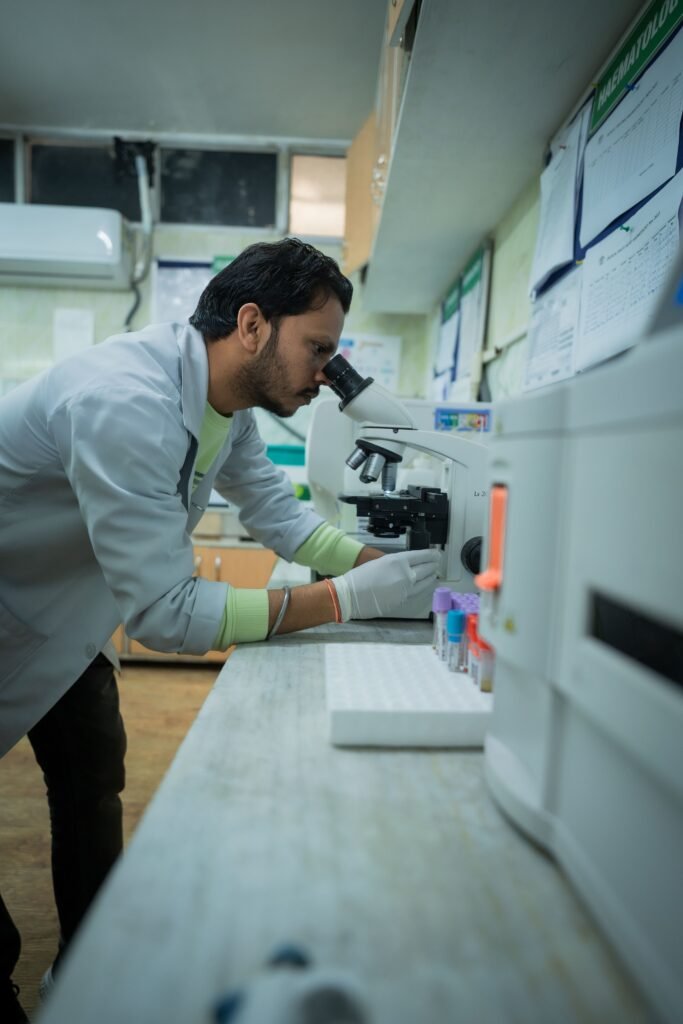

Pathology

Microbiology

Sanjeevani Multicare Hospital Gallery

Delivering the best possible treatment is something that Sanjeevani Multicare Hospital is passionate about. Whether it’s the best medical professionals, cutting-edge equipment, cutting-edge facilities, or smiling nursing staff, we think that what makes us even more outstanding is our character, the way we treat our patients as if they are our family members and friends and with the highest respect and care.

The Sanjeevani Multicare Hospital is a landmark healthcare service Institution that enjoys a unique reputation of being a popular destination for both Indian and International patients seeking treatment at an affordable cost.

Sanjeevani Multicare Hospital is the Best hospital in Amritsar, Punjab offering each patient the superior care, outstanding service, and compassion we would want for our loved ones. we also strives to lead the evolution of healthcare so that every member of the communities it serves can live a better, healthier life.